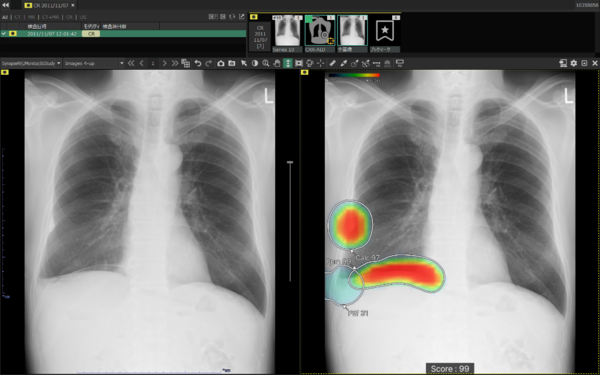

(3)所見名/スコア表示機能

従来のバージョンでは,複数の異常所見を検出した場合,検出された異常所見のうち最も確信度が高い所見のスコアのみを表示しており,各所見のスコアを確認したいという要望があった。新バージョンでは,各検出領域に対応する所見名と確信度を示すスコアを個別に表示できるようになった。これにより,医師は複数の異常所見について詳しい情報をひと目で把握でき,正確な診断を行うことが期待できる。

所見名/スコア表示

また,従来のバージョンでは,対象所見が重なった領域においてヒートマップが重なって表示されていた。そのため,異なる所見が混在している部分の識別が難しく,細かな判別や詳細な確認には限界があった。これに対し,新バージョンでは,対象所見が重なった領域についても,各所見ごとに独立した輪郭線を表示できるようになった。複数の異常所見が存在する箇所でも,それぞれの所見の範囲を明確に区別できるようになり,より詳細かつ正確な画像診断支援が期待される。

複数所見表示